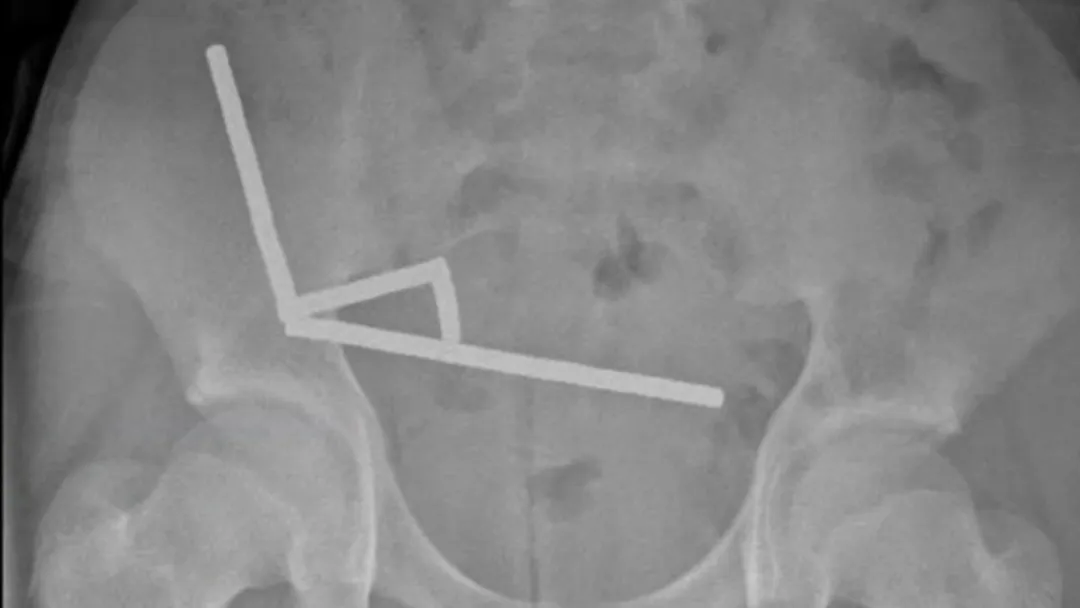

医生通过 X 光片观察到,男孩肠道的不同部位出现了四条线状的磁铁链。

腹部 X 光片显示了磁铁分布情况 来源:Lekamalage et al., NZMJ , 2025